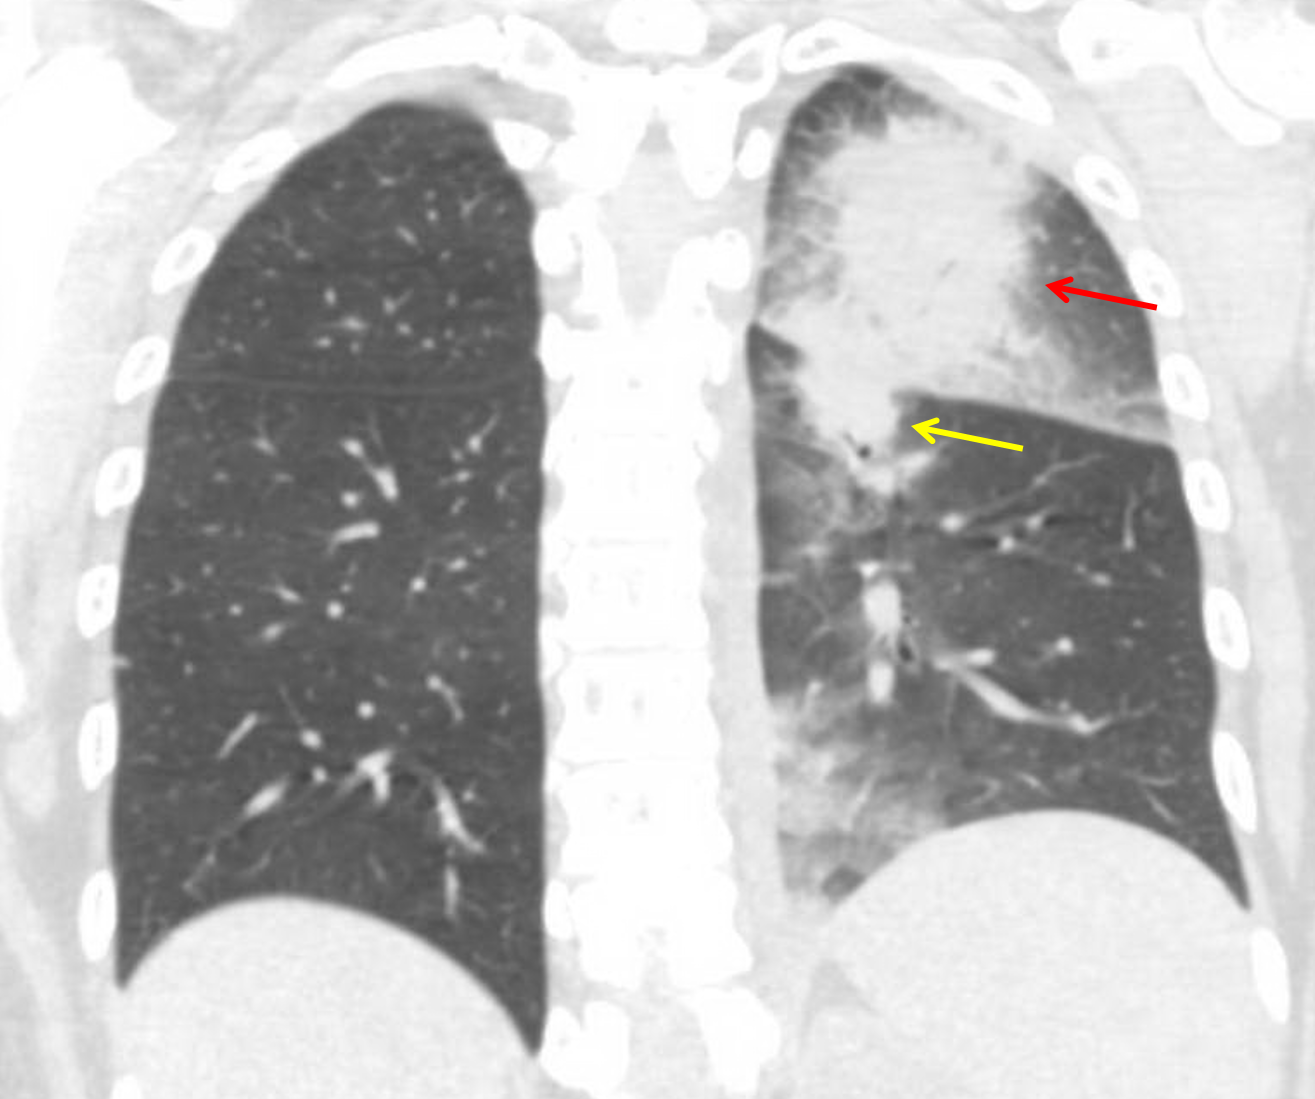

Age: 33

Sex: Female

Indication: Neutropenic fever

Sample ReportMasslike areas of consolidation with groundglass halos in the left upper and lower lobes, which are concerning for atypical infection (particularly angioinvasive aspergillosis) in this patient with neutropenic fever.

Dependent groundglass opacities in the left lower lobe could represent pneumonia, aspiration, or hemorrhage.

Trace left pleural effusion.